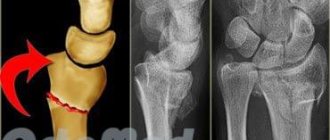

Наибольшую информацию дает рентген. Делается снимок в боковой проекции, и развитие болезни Хаглунда-Шинца врач определяет по уплотнению бугра, расширенной щели между ним и пяточной костью, неравномерной, пятнистой структуре ядра окостенения (см. фото).

На поздних стадиях заболевания на снимке хорошо просматривается губчатое вещество новой костной ткани. Разобраться в сложных случаях помогает сравнительный рентген больной и здоровой стоп. При этом важно провести дифференциальную диагностику, чтобы исключить: